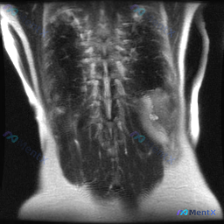

用户明确问的是「脾脏病变」,但点开图像发现——这根本不是上腹部的图像,而是一张 胸腰段脊柱区域的 MRI T2 加权冠状位。

- 脊柱与脊髓:序列尚好,脊髓/马尾信号均匀,未见明确占位或明显受压。

- 关键阳性发现:在图像左侧(即人体解剖学右侧)的背部脊柱旁软组织(肌肉层或皮下)里,有一个很明确的局灶性异常:

- 信号:以 T2 高信号为主,但混杂了稍低信号的结节样影,信号不均匀。

- 形态与边界:边界相对模糊,呈片状/不规则团块,看起来有「浸润性」,周围软组织也有点肿。

- 关键阴性(但极重要):完全没看到脾脏——脾脏在左上腹,这个层面连上腹部都没扫到。

结合现有信息,整体更倾向于:① 解剖定位错误/图像误传;② 右侧脊柱旁软组织占位,感染或恶性肿瘤均有可能,需增强扫描及活检进一步明确。